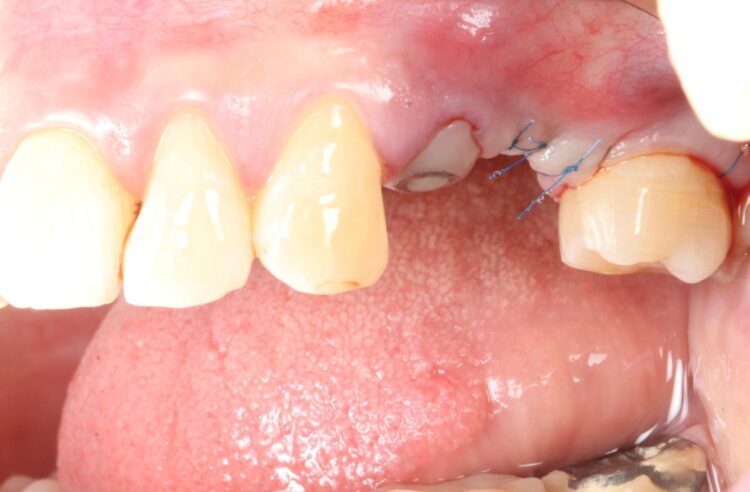

Consequently, the bone was contour-augmented, using MinerOss® Blend (BioHorizons Camlog), which provides a good combination of cortical and cancellous bone for efficient bone turnover and also maintains graft stability in the healing phase. The graft was held in place with a collagen membrane stabilised using resorbable sutures. The custom healing abutment is then placed and torqued (10Ncm) into the UL4 implant before the wound is approximated and sutured using a non-resorbable 6-0 Prolene suture.

An x-ray was taken immediately post-operatively to confirm that the temporary cylinder was seated correctly and wasn’t catching on the socket walls. This image also provided a reference for the custom healing abutment position and ensured that the bone graft material added to the jump gaps wasn’t preventing this abutment from fully seating.